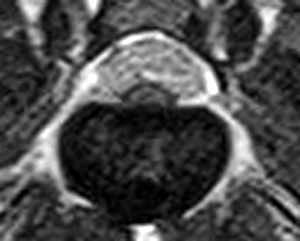

フレブルちゃん両後肢麻痺グレード5でMRI検査及び手術依頼でご紹介がありました。MRI検査で第4-5腰椎間椎間椎間板ヘルニア、右側優位な圧迫と診断し即日手術となりました。→<その2>へ続く